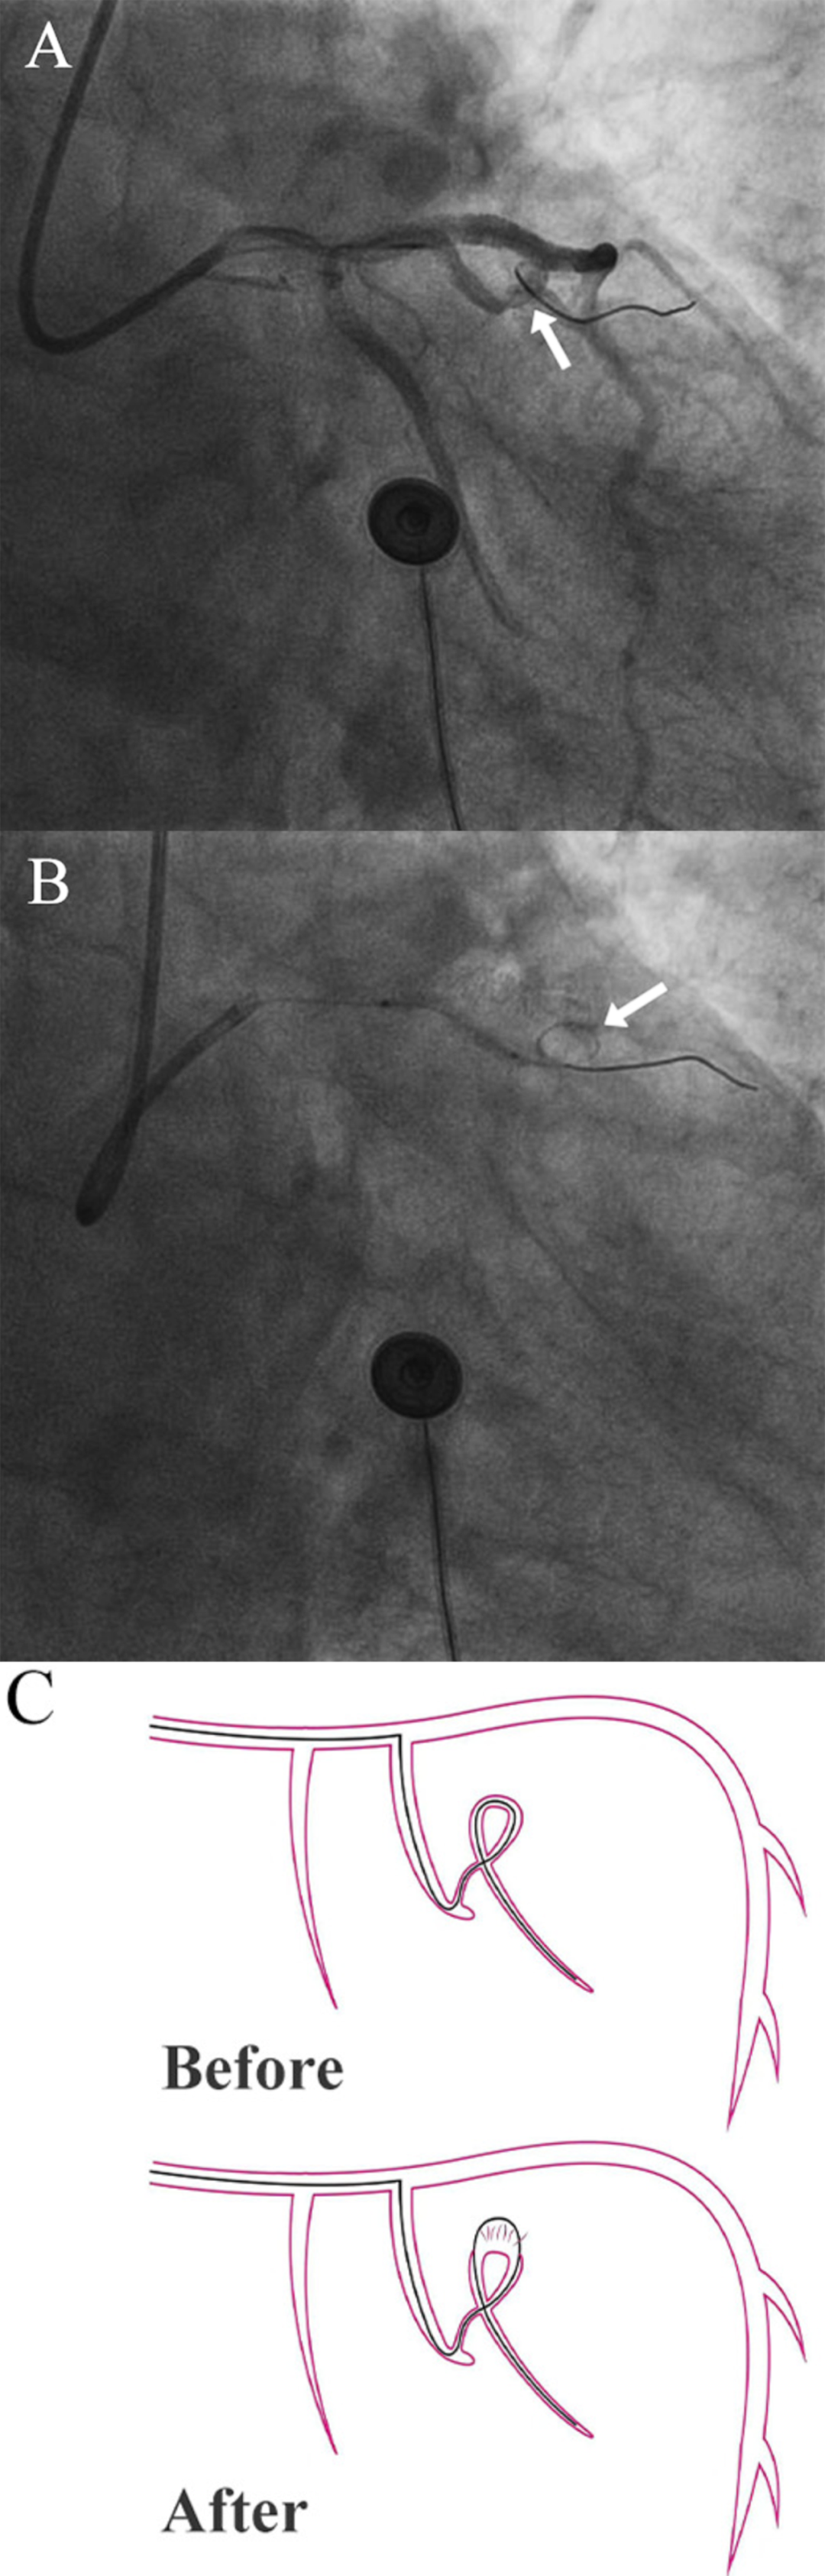

导丝通过:微导管支撑下,导丝通过近端狭窄段进入远端,在扭曲段形成螺旋状盘曲(图2A)

异常征象:球囊撤出后,原盘曲导丝突然“弹开”前移(图2B、C)

图2冠状动脉穿孔

(A)箭头指向冠状动脉破裂前盘绕的导丝(B)箭头指向冠状动脉破裂后盘绕的导丝(C)导丝切割冠状动脉的示意图。